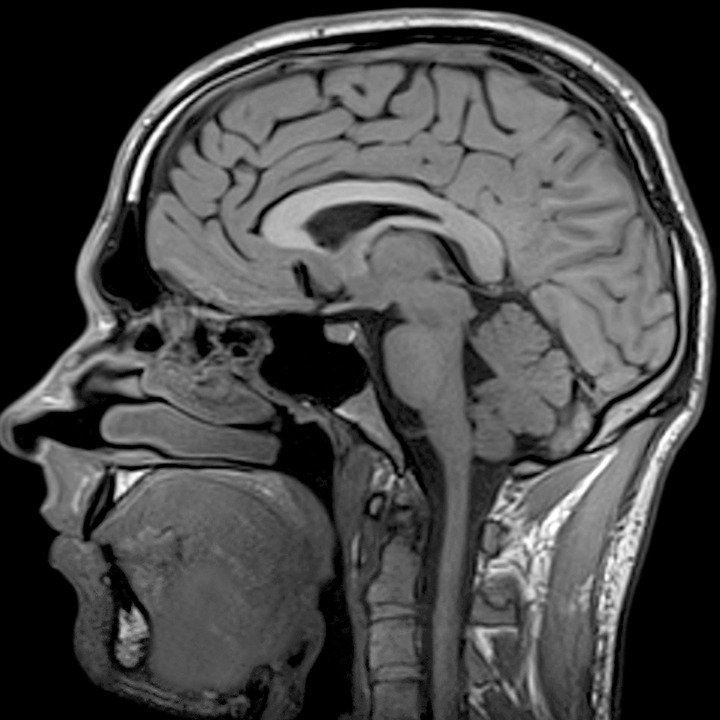

Head MRI

Magnetic resonance imaging (MRI) of the head is a painless, noninvasive test that produces detailed images of your brain and brain stem. An MRI machine creates the images using a magnetic field and radio waves. This test is also known as a brain MRI or a cranial MRI. You will go to a hospital or radiology center to take a head MRI.

An MRI scan is different from a CT scan or an X-ray in that it doesn’t use radiation to produce images. An MRI scan combines images to create a 3-D picture of your internal structures, so it’s more effective than other scans at detecting abnormalities in small structures of the brain such as the pituitary gland and brain stem. Sometimes a contrast agent, or dye, can be given through an intravenous (IV) line to better visualize certain structures or abnormalities.